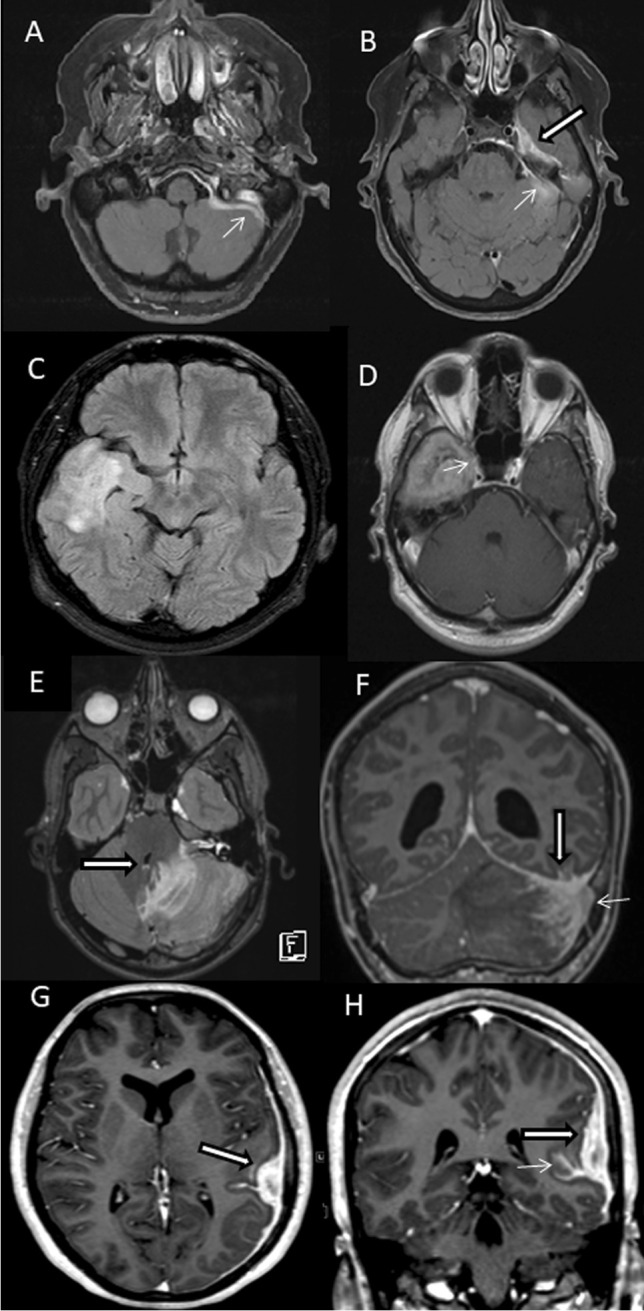

MR imaging showed tumor-like lesions in all four patients with involvement of the adjacent cerebral parenchyma in three of them. Patient 1 had a contrast-enhancing irregularly shaped extraaxial mass in the left middle fossa with infiltration of the dura extending to the posterior fossa (Fig. 1A, B). In patient 2, FLAIR-weighted imaging showed extensive cerebral edema in the right middle and superior temporal gyrus (Fig. 1C) while gadolinium-enhanced T1-weighted imaging revealed a contrast-enhancing solid mass in the inferior temporal gyrus extending to the cavernous sinus (Fig. 1D). In patient 3, T2-weighted images demonstrated extensive cerebral edema in the left cerebellar hemisphere with compression of the fourth ventricle (Fig. 1E) and T1-weighted gadolinium-enhanced imaging showed a heterogeneously contrast-enhancing tumor adjacent to the dura of the transverse sinus (Fig. 1F). In patient 4, T1-weighted gadolinium-enhanced images showed focal thickening of the dura over the left hemisphere and a strongly contrast-enhancing subdural mass lesion with finger-like extension into the adjacent sulci (Fig. 1G, H).

Fig. 1.

A, B Patient 1, 67-year-old woman: axial gadolinium (Gd)-enhanced fat-saturated T1-weighted MRI shows a heterogeneously contrast-enhancing extraaxial mass in the left middle fossa (large arrow) with infiltration of the dura extending to the posterior fossa (small arrows). C, D Patient 2, 30-year-old man: axial FLAIR-weighted MRI shows extensive cerebral edema in the middle and superior temporal gyrus. Axial Gd-enhanced T1-weighted MRI demonstrates homogenous contrast enhancing solid mass in the inferior temporal gyrus extending to the cavernous sinus (small arrow). E, F Patient 3, 16-year-old woman: T2-weighted axial images show extensive cerebral edema in the left cerebellar hemisphere with compression of the fourth ventricle (large arrow in E), and Gd-enhanced fat-saturated T1-weighted MRI shows heterogeneously contrast enhancing process infiltrating the cerebellar sulci, dural sinuses (small arrow), the left sided tentorium cerebelli and the ipsilateral sulci of the inferior temporal gyrus (large arrow in F). G, H Patient 4, 15-year-old man: T1-weighted gadolinium-enhanced axial and coronal MRI show a strongly contrast-enhancing left temporal tumor (large arrows) with finger-like extension to the adjacent sulci (small arrow)